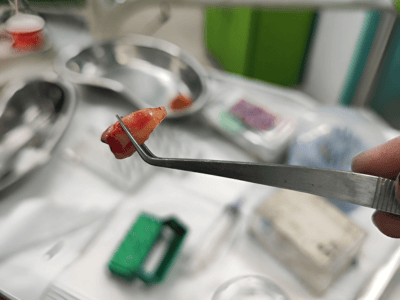

provides expert treatment for gum diseases, receding gums, and dental implant procedures using the

high standards of hygiene and comfort. Her expertise includes laser dentistry, cosmetic smile

From routine checkups to complex gum treatments, dental implants, laser dentistry, root canal treatments (RCT), and smile

Dr. Bhardwaj specializes in Periodontics, offering treatments for gum diseases, dental implants, laser dentistry, root canal treatments (RCT), teeth whitening, smile makeovers, and general dental care.